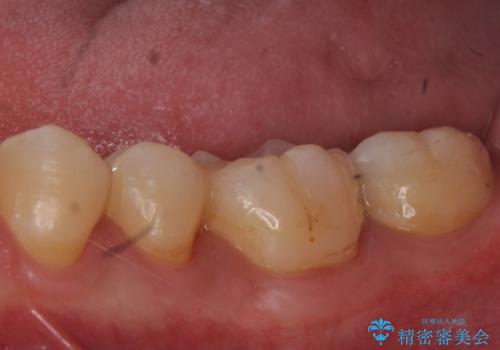

e-maxインレーによる治療

- 定期検診で来院してレントゲンを撮ったところ

歯と歯の間にう蝕ができていました。

拡大鏡下でう蝕を全て除去してe-maxインレーにて治療を行いました。

- e-maxインレー 7.7万円 費用は治療当時の料金となります